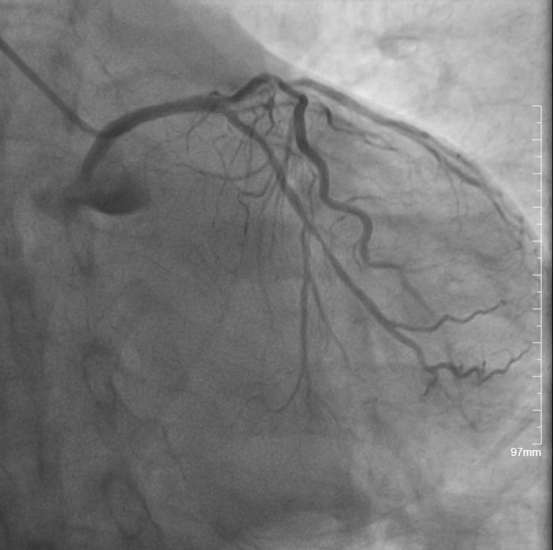

◆成功开通右冠状动脉急性闭塞病变